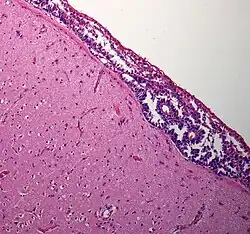

| Meningeal carcinomatosis: tumor cell clusters in the subarachnoid space in a brain biopsy | |

Pathology

There are three anatomic patterns by which the tumor can spread in the subarachnoid space. More than one pattern may coexist in the same patient.

First, there may be plaque-like deposits of cells in the leptomeninges with invasion of Virchow-Robin spaces and, usually, the shedding of tumor cells into the cerebrospinal fluid.

Second, there may only be a thin coating of meninges, in some cases with only a single cell layer, but also with shedding of tumor cells into the cerebrospinal fluid. Third, there may be a pattern of nodular deposits of tumor on cranial and spinal nerve roots, frequently without tumor cells being shed into the cerebrospinal fluid.

The first and third patterns are common in solid tumors whereas the second occurs most frequently with leukemia and lymphoma.[7]